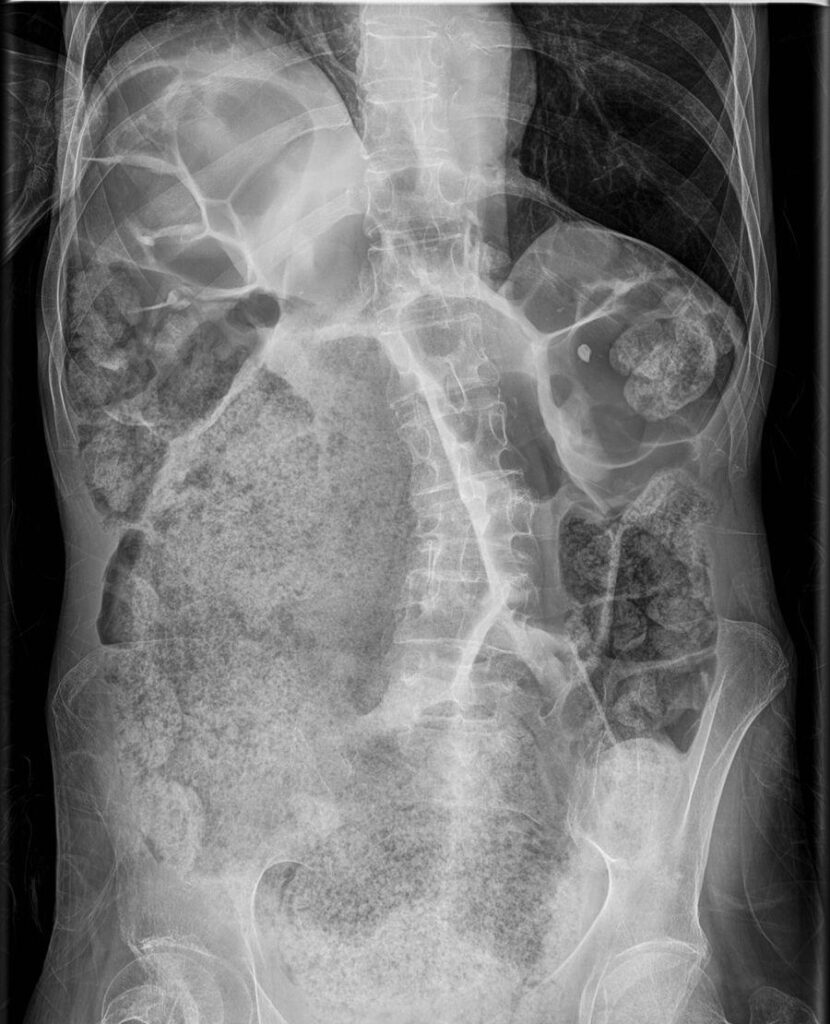

La diverticulosis colónica es una afección caracterizada por la formación de pequeñas protuberancias o divertículos en la pared del colon. Su prevalencia aumenta significativamente con la edad, observándose un incremento…